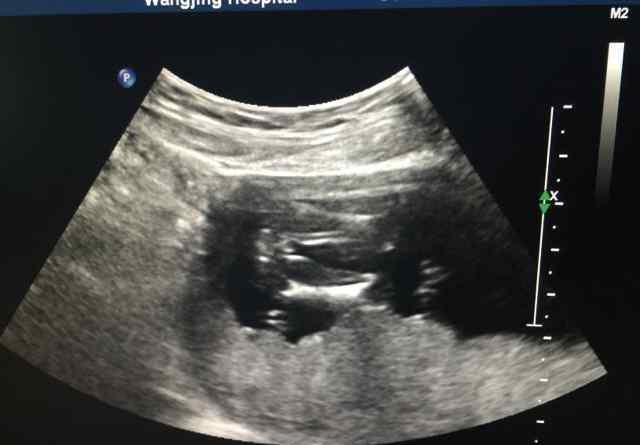

b超的重要数据如下:

124双顶直径19腹围66肱骨11股骨10臀长66 NT1.6

孕期b超图1